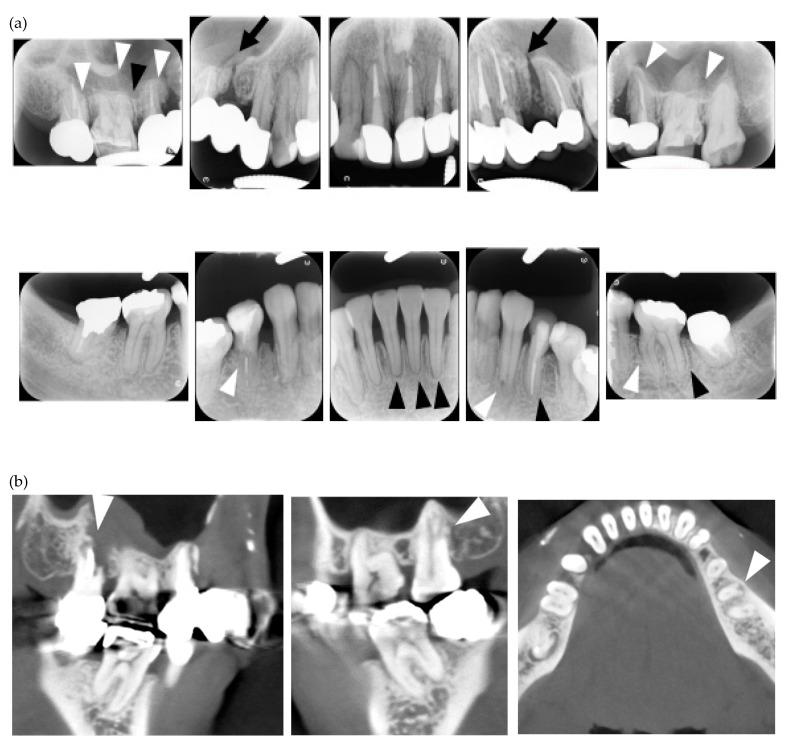

Root resorption was detected by dental X-rays, panoramagraphy or cone beam computed tomography (CBCT). The prevalence of systemic and oral manifestations was examined by rheumatologists and dentists, respectively. Autoantibodies were investigated using laboratory tests.

MERR was detected in four out of the 41 patients (9.8%) who participated in the present study. The prevalence of digital ulcers was significantly higher in patients with MERR (MERR vs non-MERR, 75% vs 16.2%, p < 0.05), whereas that of other systemic manifestations was not. The prevalence of face skin sclerosis (100% vs 10.8%, p < 0.01), calcinosis at the facial region (75% vs 0%, p < 0.01), limited mouth opening (75% vs 18.9% p < 0.05), temporomandibular disorder symptoms (50% vs 2.7%, p < 0.05), and tongue rigidity (75% vs 2.7%, p < 0.05) was significantly higher in patients with MERR.